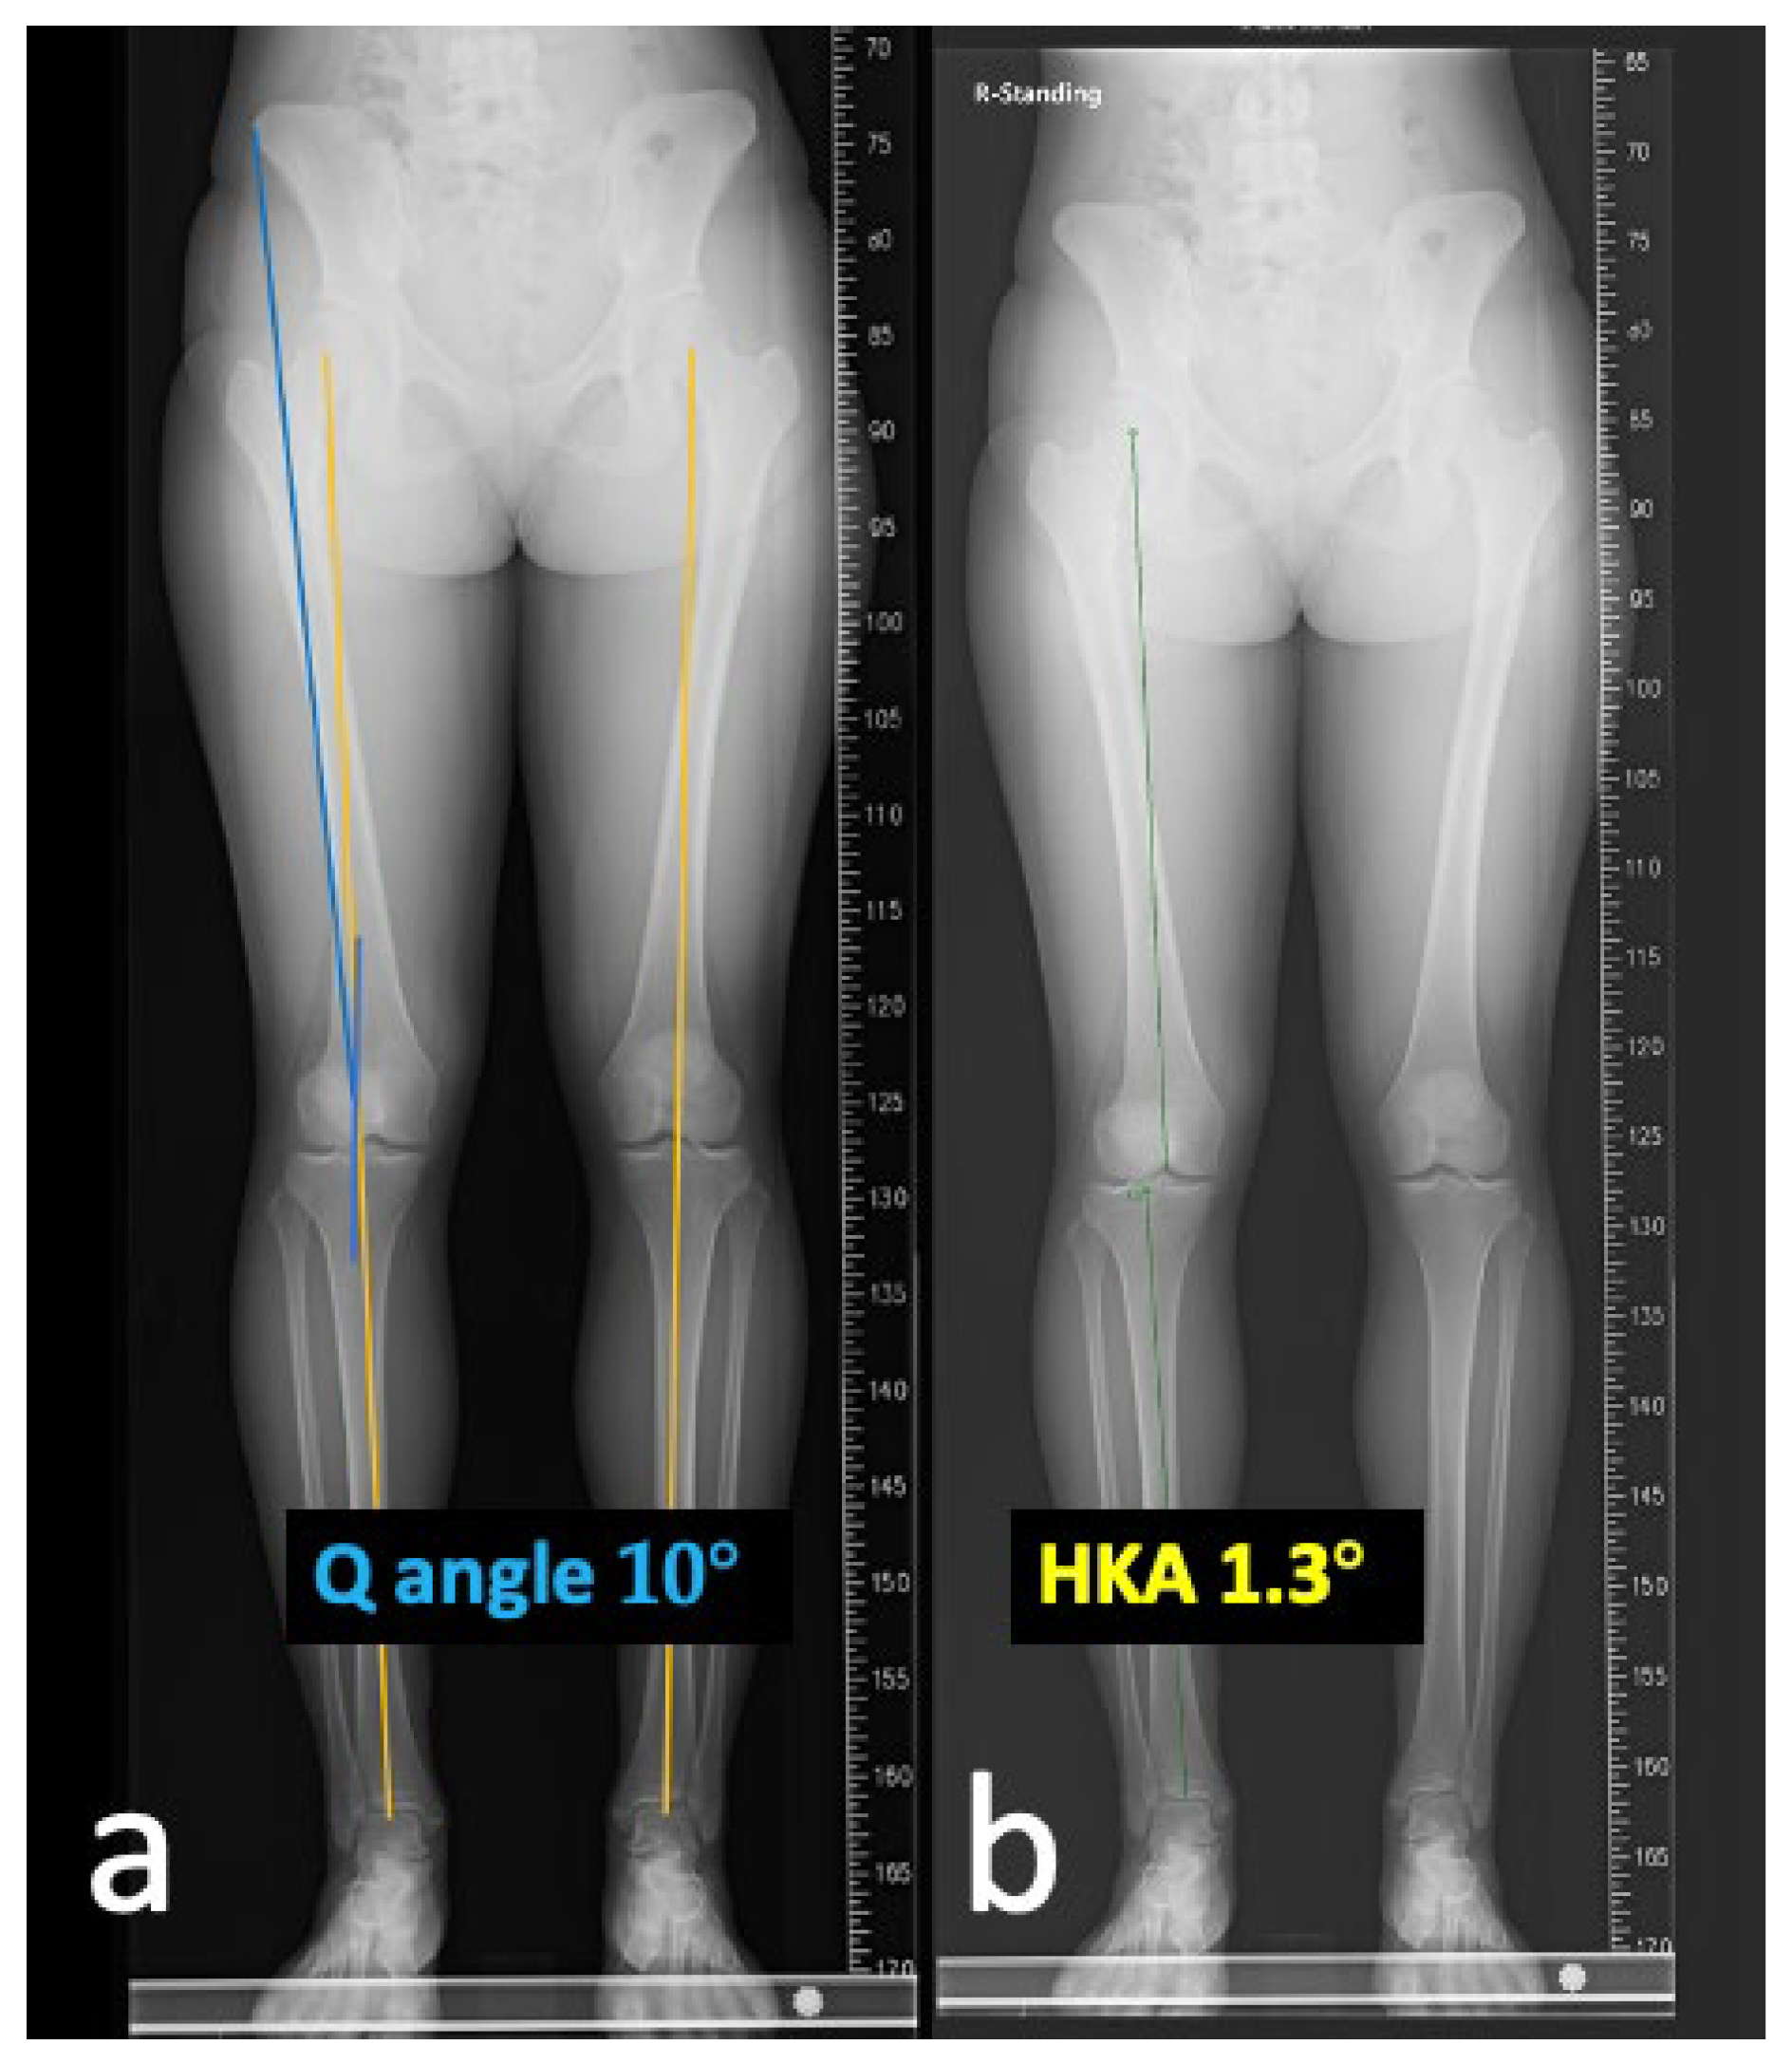

2.1. Case